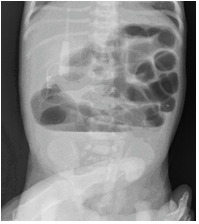

Child didn't pass meconium even after 24 hours, an abdominal radiograph was taken which showed multiple dilated bowel loops with multiple air fluid levels, no rectal gas was seen suggestive of intestinal obstruction, a possibility of meconium ileus or small bowel atresia was kept in mind (Figure 3).

Figure 3: Plain radiograph of the abdomen showing gas filled dilated featureless bowel loops, suggestive of intestinal obstruction with no calcification in the abdomen